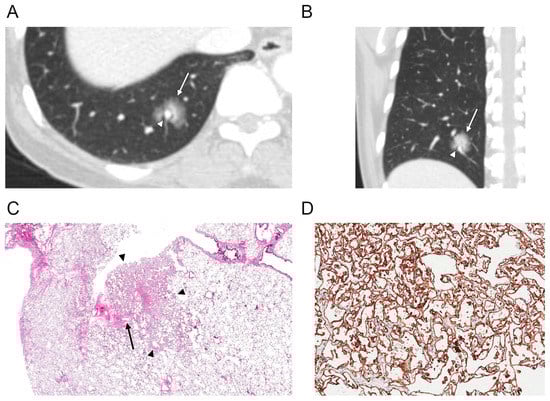

| Nodule density | |

| Ground-glass | 1 (6) |

| Part-solid | 15 (88) |

| Solid | 1 (6) |

| Contour | |

| Smooth | 16 (94) |

| Margin | |

| Well-defined | 8 (47) |

| Ill-defined | 9 (53) |

| Perivascular lucency | 2 (12) |

| Air bronchogram | 10 (59) |

| Enhancement ** | |

| Hypoattenuation | 14 (93) |